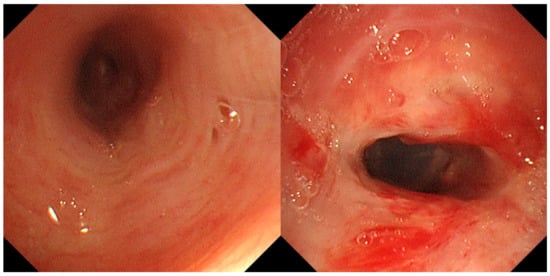

A 74-year-old woman was admitted to our hospital with dyspnea and chest pain. She had hypertension, type 2 diabetes mellitus, heart failure, persistent atrial fibrillation, and chronic obstructive pulmonary disease (COPD). The patient did not use an inhalant for COPD because of low adherence to inhalation therapy. Human immunodeficiency virus testing was negative. On the second day of admission, she complained of chest pain and showed a decrease in consciousness. Torsade de pointes and ventricular fibrillation were observed. She underwent intensive care unit (ICU) treatment for 10 days, including mechanical ventilation, direct-current cardioversion, and a temporary pacemaker. The patient received prednisolone from 5 mg to 10 mg per day with inhaled budesonide/salbutamol/ipratropium for two months from the day of ICU admission to treat the COPD exacerbation and control dyspnea. After being transferred to the general ward, the patient remained stable with tapering and discontinuation of steroid administration. The patient developed throat discomfort on the 68th day of hospitalization. Since then, her dyspnea gradually worsened without desaturation and CO2 retention. On the 76th day of hospitalization, the patient complained of sustained throat discomfort and dyspnea with stridor. Neck computed tomography revealed a narrowing of the proximal trachea with a diffuse wall thickening and intraluminal irregularity (Figure 1), and video laryngoscopy detected a tracheal mass-like lesion. On the same date, acute respiratory failure occurred (the oxygen saturation by pulse oximeter was 56%, and the respiratory rate was 32 breaths per min). CO2 retention was detected in the arterial blood gas analysis (pH: 7.037, PaCO2: 66.1 mmHg, PaO2: 205.3 mmHg) at 15 L/min via reservoir bag. The patient was transferred to the ICU for mechanical ventilation. There was no evidence of nosocomial pneumonia in the chest X-ray, and serum C-reactive protein was normal (<0.5 mg/dL). No severe obstructive respiratory pattern was observed on the flow graph of the ventilator monitoring, and the CO2 retention immediately improved after endotracheal intubation in low grade pressure support. On the second day after intubation, chest computed tomography showed an aggravation of the multifocal diffuse tracheal wall thickening with luminal narrowing (Figure 2A) and a new-onset peribronchial ill-defined consolidation in the right upper lobe (Figure 2B). The piperacillin-tazobactam was initially administered for treatment of pneumonia. Bronchoscopy revealed a proximal tracheal narrowing with multiple ulcerations of the tracheal mucosa surrounded by an erythematous margin (Figure 3A). Multiple biopsies were performed at the base and margin of the ulceration (Figure 3B). Microscopically, reactive squamous atypia was observed in the background of the ulcer and granulation tissue (Figure 4A). In the squamous epithelium, numerous keratinocytes with virus-infected changes, including ground glass nuclei and nuclear molding, and multinucleated giant cells were observed (Figure 4B). Immunohistochemistry showed positive results for the anti-HSV antibody. A few viral cytopathic cells were noted in the granulation tissue, which were positive for the anti-CMV antibody (Figure 4C). The CMV real-time polymerase chain reaction (PCR) in the bronchial alveolar lavage fluid was also positive (31,775 copies/mL). Therefore, intravenous ganciclovir (300 mg twice daily), which is effective against HSV and CMV, was administered for 44 days. Despite the cessation of the sedative drugs, the patient’s consciousness did not improve. Brain magnetic resonance imaging revealed a multifocal petechial hemorrhage in the bilateral temporo-parietal lobe and left insula and minimal subdural hygroma along the left cerebral convexity. These findings were consistent with hemorrhagic encephalitis. The cerebrospinal fluid examination was within normal limits (white blood cells, 1 cells/µL; protein, 43 mg/dL). The viral PCR results for enterovirus, CMV, HSV, and varicella-zoster virus were all negative. On the 19th day after intubation, a percutaneous dilatational tracheostomy was performed for the tracheal stricture. The patient was transferred to the general ward on the 29th day after ICU readmission. A follow-up bronchoscopy was performed about every two weeks. On the 44th day of ganciclovir therapy, the follow-up bronchoscopy showed an improvement in the ulceration with scars (Figure 5). Microscopically, no lesions were suspected from viral infection.

Figure 3. Bronchoscopic images. (A) Multiple deep ulcerations are noted in the proximal trachea. (B) Multiple biopsies were performed at the ulcer base and elevated ulcer margin.